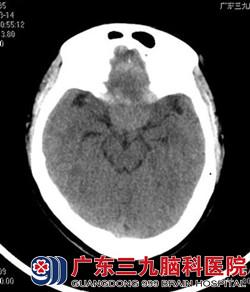

行头颅MR检查提示鞍结节脑膜瘤,大小约4*4cm,完善相关检查后,由鲁明主任主刀,在全麻下行冠状切口右额纵裂入路鞍结节脑膜瘤切除术,术中显微镜下见灰白色肿瘤组织位于鞍上,肿瘤基底部位于鞍结节,质软,双侧视神经、嗅神经被肿瘤压迫明显,大脑前动脉被肿瘤压迫上移,垂体柄位于肿瘤后下方,术中神经、血管均保留完整,肿瘤显微镜下全切,手术顺利结束,术后患者经过专科治疗护理,诉视力、视野明显较术前好转,康复出院。术后病理结果为:脑膜皮细胞型脑膜瘤(WHO I级)。

术后